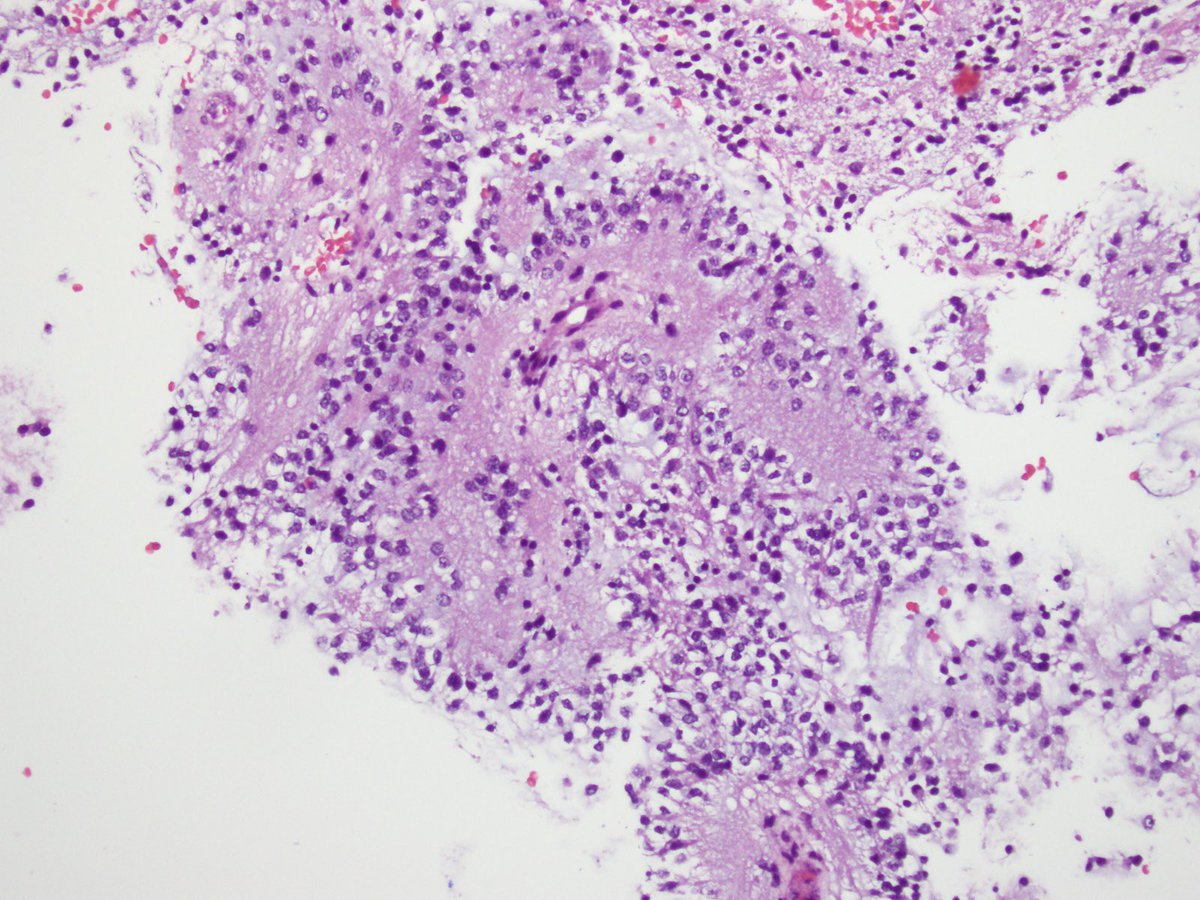

You don’t need special stains or fancy molecular testing to diagnose this #brain #tumor, located in the fourth ventricle. Flex your histology skills and tell me what you see! @NU_Pathology #neuropath πŸ§ πŸ”¬

7

27

110